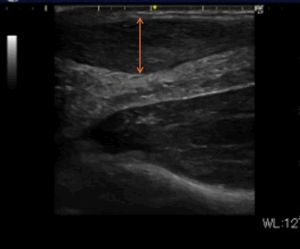

・超音波検査:アキレス腱の肥厚、炎症、微小断裂の有無を評価

※アキレス腱実質部に肥厚と内部高エコーが混在している。